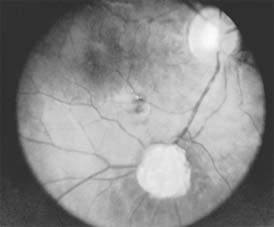

Astrocytic hamartomas are translucent to whitish retinal and optic nerve head tumors most frequently associated with tuberous sclerosis (Bourneville's disease) (Figure 10-31). They may also be associated with neurofibromatosis-1 and -2 or may occur as isolated findings. These tumors are congenital. They may grow slowly and, as they mature, become calcified, acquiring a mulberry configuration.

Figure 10-31

Figure 10-31: Retinal astrocytic hamartoma.